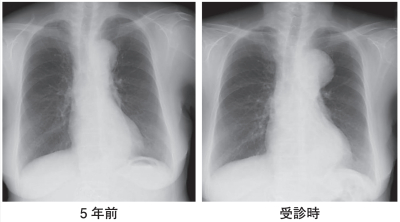

血液所見:赤血球 391 万、Hb 12.7 g/dL、Ht 36 %、白血球 8,300、血小板 23 万。血液生化学所見:総蛋白 7.2 g/dL、アルブミン 3.5 g/dL、総ビリルビン 0.5 mg/dL、AST 25 U/L、ALT 17 U/L、尿素窒素 21 mg/dL、クレアチニン 1.1 mg/dL。CRP 0.1 mg/dL。5 年前と今回受診時の胸部エックス線写真を別に示す。